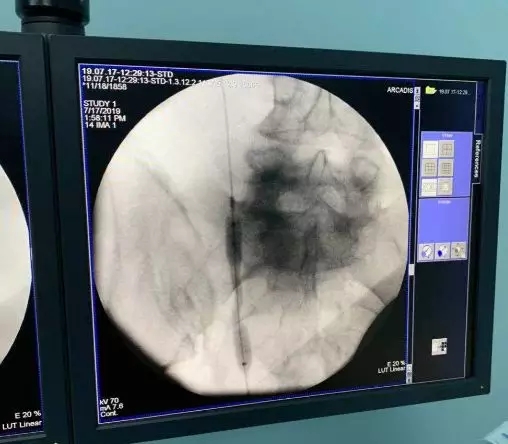

为保护患者右肾功能以及治愈右侧输尿管狭窄,经科室讨论后,决定Ⅰ期先行右输尿管镜检+右侧输尿管狭窄球囊扩张术;Ⅱ期行右侧输尿管狭窄ALLIUM支架植入术。Ⅰ期术中发现右侧输尿管中段迂曲并瘢痕狭窄形成,使用球囊扩张器将狭窄部位扩张。

术中检查发现明显“蜂腰征”,提示右侧输尿管中段狭窄

术中使用输尿管球囊扩张器将狭窄部位扩开